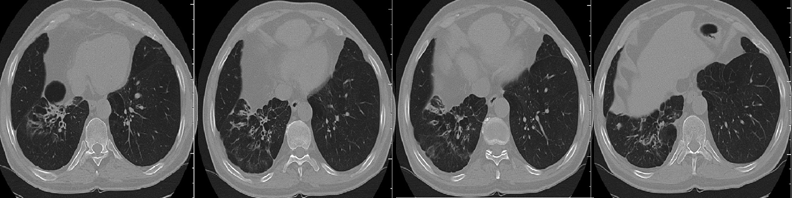

Для достоверной диагностики сложных случаев требуется рентгеновская компьютерная томография (РКТ). Она позволяет получать поперечные сканы (срезы) тела, прилежащие друг к другу, на всем протяжении грудной клетки — от верхушек легких до базальных отделов — без «немых зон». РКТ более достоверно отображает локализацию, характер патологического процесса, его связь с соседними тканями.

За одно исследование получают от 40 до 1 000 отдельных сканов, рентгенолог их оценивает, сравнивает с соседними и впоследствии выполняет мультипланарные реконструкции. Эффективная средняя эквивалентная доза при проведении РКТ — 2,9 мЗв (в зависимости от конституции пациента — от 1,8 до 13 мЗв).

Поствоспалительные изменения в нижней доле правого легкого. Бронхи сближены, просвет неравномерно расширен, стенки фиброзно утолщены. Перибронхиальные фиброзные изменения в легочной ткани, плевральные пластические наслоения.

Изменения в верхней доле — как в нижней. Однако в проекции 3-го сегмента — участок плевроплевмоцирроза с расширенными, деформированными бронхами; полостное образование с фиброзированными стенками. Важно: при столь длительном «туберкулезе» даже при наличии полости деструкции нет характерных очагов и обызвествлений.